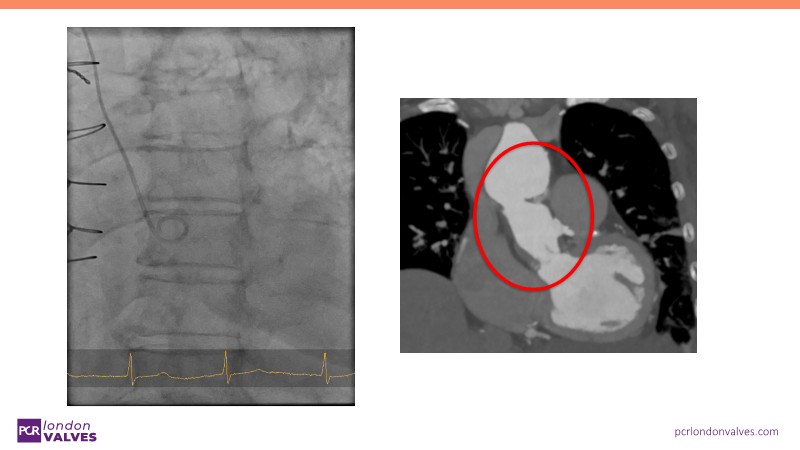

This session offers an in-depth review of complex TAVI cases, focusing on overcoming clinical challenges and achieving optimal outcomes with the Evolut FX+ device. Participants will learn about recent advances in TAVI indications for younger and asymptomatic patients, strategies for managing TAV in surgical aortic valve (SAV) patients including redo TAVI, and explore technological innovations designed to address complex anatomical scenarios.